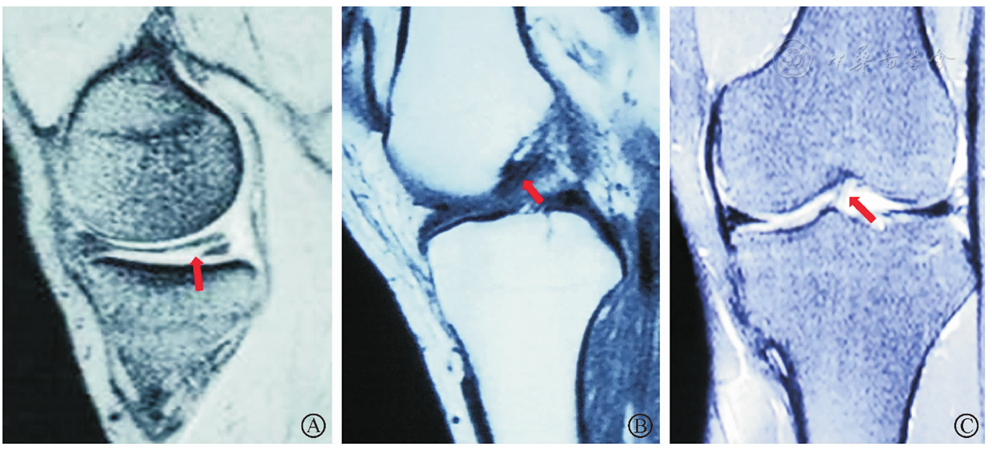

图2 左膝关节MRI检查。图A内侧半月板损伤;图B矢状位示AMMFL(内侧半月板前角附着部)为低信号条带状结构;图C冠状位示AMMFL起自内侧半月板前角,止于髁间窝外侧壁